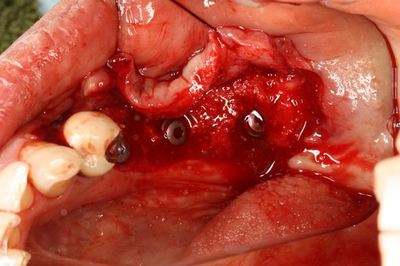

本日のオペは下歯槽神経管に近接していますので極度の集中力が必要です。

予定位置に無事埋入を終えました。

インプラントは私が信頼を置くスイスのストローマン社製です。

骨欠損の部分はまだインプラントネックが露出していますので対処をします。